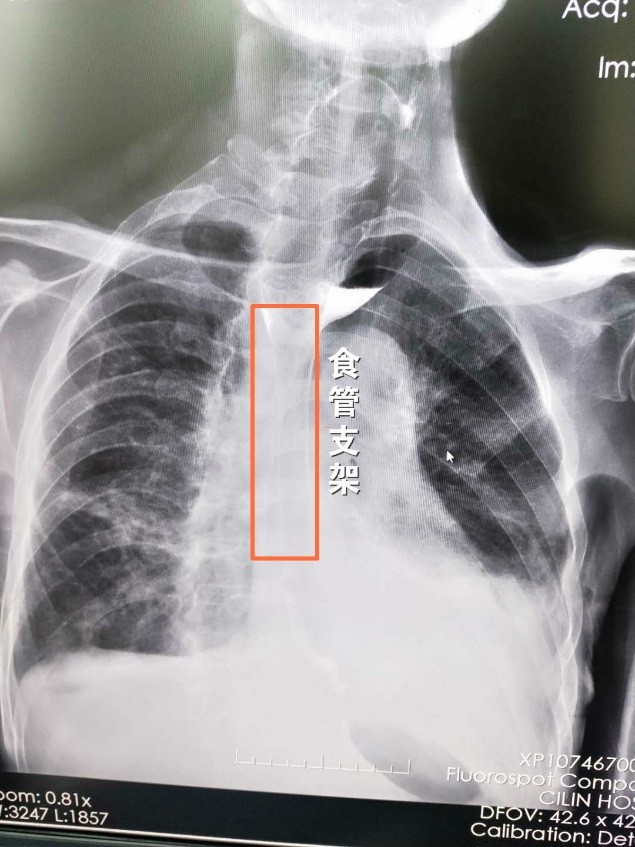

于军主任研究了黄大爷的病情后,为黄大爷做了食管支架,并为他处理了癌痛问题,到了今天,黄大爷已经能够正常地喝水吃粥了。